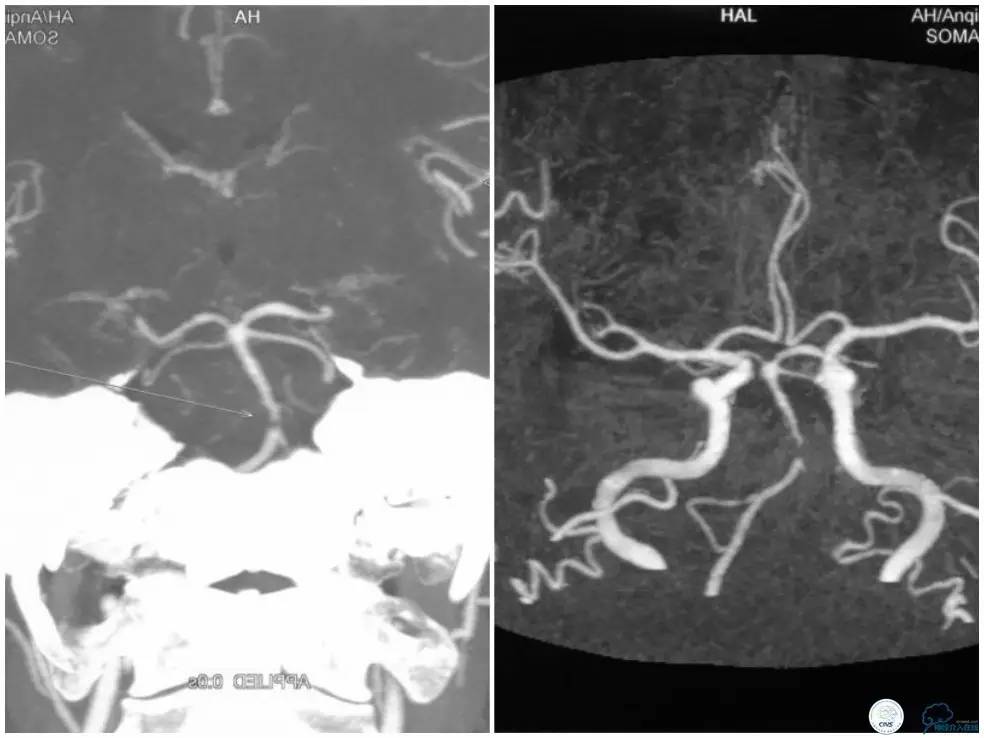

颅内动脉粥样硬化性狭窄多为偏心性狭窄分布于管腔某一壁。但我们也可见突出于管腔内的狭窄,造影显示狭窄轮廓不清,某些投造体位可见充盈缺损(图1,来自秦皇岛市第一医院,杨大为主任提供),类似“蜂巢样”改变,或者呈“夹层样”改变。本周我们汇报病例系一例基底动脉“蜂巢样”狭窄支架治疗的过程。

CTA示基底动脉重度狭窄(图3)。

图3